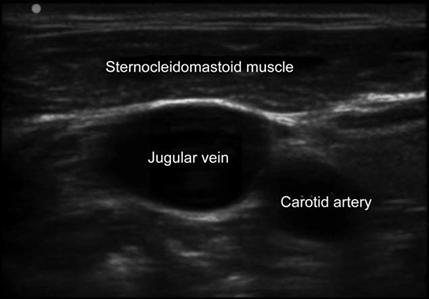

Technological sophistication of US machines varies significant, although the most basic models are good for vascular accesses. US modes for identifying and localizing vessels for catheterization are B mode (bidimensional) and Doppler for flow analysis (arterial or venous). Selecting the appropriate linear high-frequency (5-12MHz) probe is critical for obtaining high-quality images; high-frequency provides better resolution of the tissues lying close to the skin surface, which is ideal for vessel visualization10 (Fig. 2).

The structures covered by the US beam underneath the left side of the probe marker (indicated by a light or notch on the side of the probe) always come up on the screen from left to right. Therefore, probes have markings that help with correct orientation. Moving the probe to the left or to the right while watching the image should help confirm the adequate orientation. 15

Transverse and/or longitudinal planes can be used for localization of the selected vein and catheter placement. 16 The transverse position (short axis) is useful for accessing vessels near the skin surface such as the internal jugular vein. 17,18 For deeper vessels, as is the case with the common femoral vein, a combined approach may be used, starting with the transverse position to identify the vessel, followed by rotation to the longitudinal view, initial needle advancement, and cannulation completion. 19